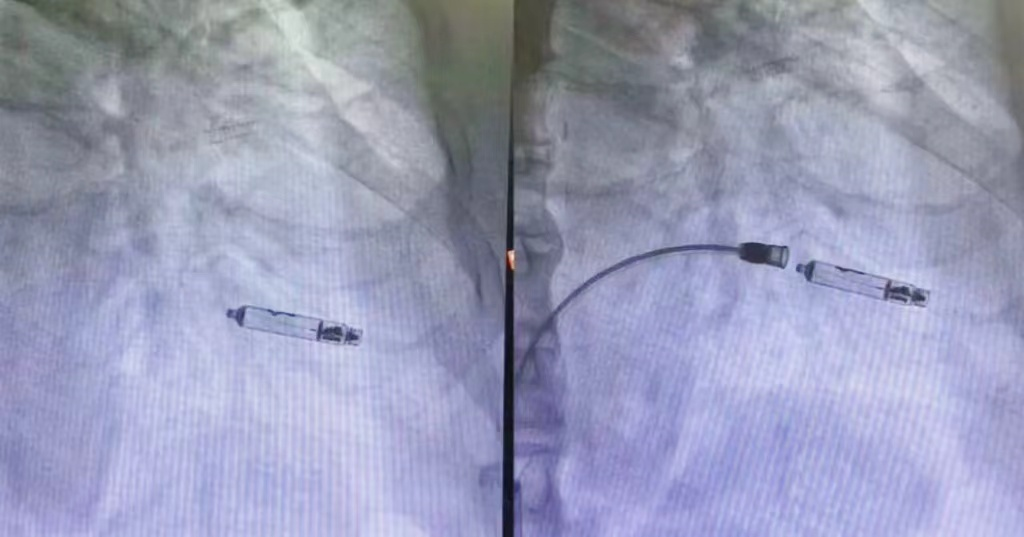

手术室内,无影灯下肃穆庄严。医生们全神贯注,通过股静脉将那颗精密如艺术品的起搏器,轻柔地植入心脏右心室。没有切口,不留囊袋,唯有科技的光芒如静谧的星光,默默守护着生命的律动。